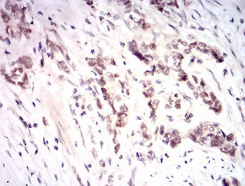

NFE2L2 Mouse Monoclonal antibody[1A6G6]

IHC    1/200 - 1/1000